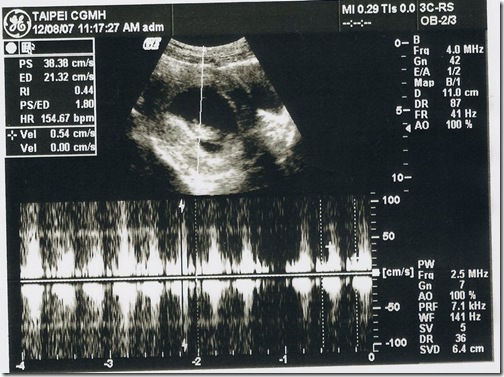

| 身長 | 6.4cm | OK |

| 心跳 | 150下/分鐘 | OK |

從右邊的數據可以看到頭臀長己經有6.4公分了